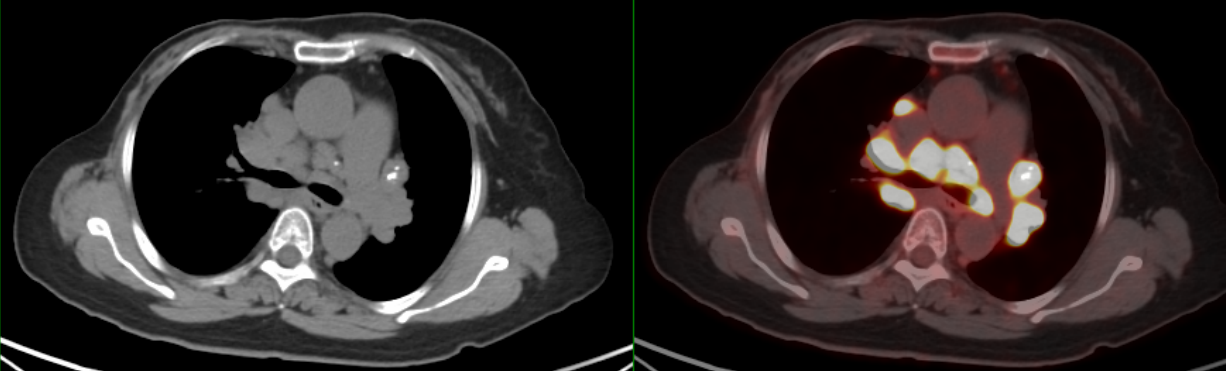

PET/CT示:雙側(cè)鎖骨上、縱隔、胸骨后、雙肺門(mén)、雙側(cè)肋骨旁、腹腔、腹膜后、盆腔及左側(cè)腹股溝見(jiàn)多枚代謝異常增高淋巴結(jié),較大者約3.4×2.1cm,SUVmax約20.7。

18F-FDG PET/CT在腫瘤患者的全身評(píng)估中具有顯著優(yōu)勢(shì),在乳腺癌術(shù)后出現(xiàn)縱隔和肺門(mén)腫大淋巴結(jié)時(shí),不但能顯示淋巴結(jié)全身的分布特征,且能更早發(fā)現(xiàn)胸外病變及隱匿性病變,同時(shí)體現(xiàn)不同部位淋巴結(jié)的FDG攝取程度,判定病灶活動(dòng)性,有利于結(jié)節(jié)病與乳腺癌術(shù)后復(fù)發(fā)或淋巴瘤等的鑒別診斷。由于結(jié)節(jié)病的診斷主要依靠組織病理學(xué)活檢,PET/CT可以提示適合的活檢部位,提高活檢診斷成功率。

此例患者由于乳腺癌的病史,臨床初步懷疑轉(zhuǎn)移。PET/CT顯示縱隔、肺門(mén)淋巴結(jié)腫大,且呈對(duì)稱(chēng)性分布,密度均勻,邊界清晰,無(wú)明顯融合,F(xiàn)DG高攝??;此外可見(jiàn)多發(fā)腹盆部,頸部淋巴結(jié)次之,分布較散,體積及FDG攝取小于縱隔和肺門(mén)淋巴結(jié),也不是乳腺癌術(shù)后易轉(zhuǎn)移的部位。綜上考慮符合結(jié)節(jié)病表現(xiàn),最終得到病理證實(shí),患者因此避免了不必要的抗腫瘤治療。